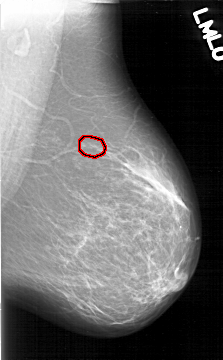

D_4195_1.LEFT_MLO

LEFT_MLO LINES 6466 PIXELS_PER_LINE 4006 BITS_PER_PIXEL 12 RESOLUTION 43.5 OVERLAY

FILE: D_4195_1.LEFT_MLO.OVERLAY

TOTAL_ABNORMALITIES 1

ABNORMALITY 1

LESION_TYPE CALCIFICATION TYPE AMORPHOUS DISTRIBUTION CLUSTERED

ASSESSMENT 0

SUBTLETY 3

PATHOLOGY BENIGN

TOTAL_OUTLINES 1